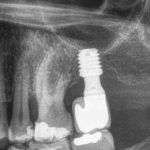

Chirurgia guidata: strumento indispensabile nella pianificazione chirurgica e protesica

In questo case report realizzato dal Dott. Gabriele Vaccaro, viene descritto un intervento di riabilitazione implantare di un dente singolo effettuato con pianificazione digitale....